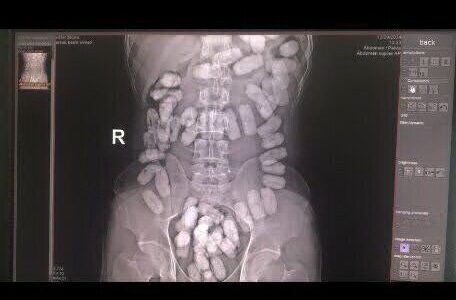

در راستای برخورد قاطع با قاچاقچیان مواد مخدر و جلوگیری از ورود مواد مخدر به داخل کشور، مرزبانان ایست و بازرسی ۱۷ شهریور در حین بازدید و بازرسی مسافران در بخش ورود به کشور به یک تبعه افغانستانی مشکوک شدند.به گزارش همشهری آنلاین، در راستای برخورد قاطع با قاچاقچیان مواد مخدر جلوگیری از ورود مواد مخدر به داخل کشور، مرزبانان ایست و بازرسی ۱۷ شهریور در حین بازدید و بازرسی مسافران در بخش ورود به کشور به یک تبعه افغانستانی مشکوک شدند.جانشین فرمانده مرزبانی خراسان رضوی گفت: ۵۵ بسته مواد مخدر آببندی شده به وزن ۵۵۰ گرم از نوع هرویین پودری که در معده جاسازی شده بود، از یک تبعه خارجی در هنگ مرزی تایباد کشف شد.سرهنگ حسین سیفی روز دوشنبه افزود: در راستای برخورد قاطع با قاچاقچیان مواد مخدر و جلوگیری از ورود مواد مخدر به داخل کشور، مرزبانان ایست و بازرسی ۱۷ شهریور در حین بازدید و بازرسی مسافران در بخش ورود به کشور به یک تبعه افغانستانی مشکوک شدند.وی بیان کرد: این فرد ۵۵ بسته هروئین از طریق بلعیدن به همراه داشت که متهم دستگیر و به همراه مواد کشف شده تحویل مراجع قضایی شد.